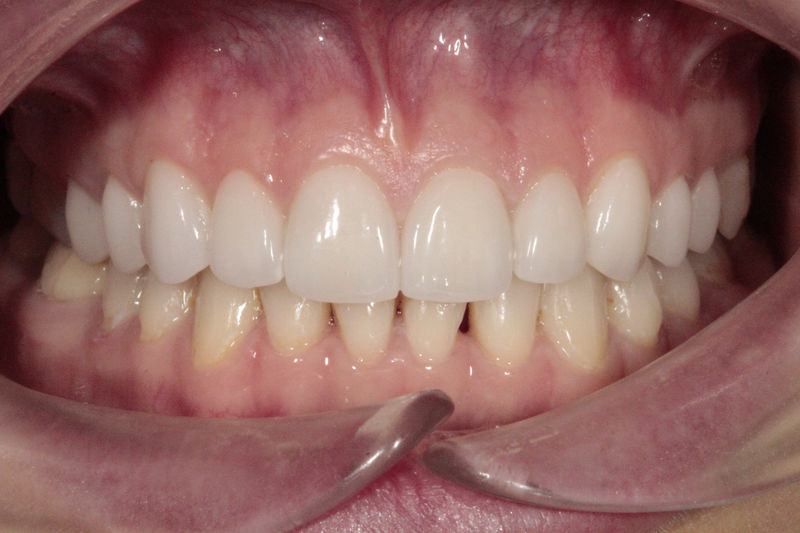

Cirugía ortognática, implantes, carillas y coronas,